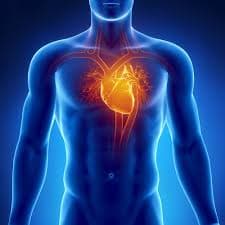

Antes de mais nada, a Cardiologia clínica concentra o cuidado médico contínuo do coração, com foco em prevenção, diagnóstico preciso e acompanhamento individualizado.Além disso, a especialidade […]

Antes de mais nada, a Cardiologia reúne práticas essenciais para prevenção, diagnóstico e acompanhamento das doenças do coração.Além disso, a especialidade orienta decisões clínicas baseadas em […]

Antes de mais nada, escolher um Médico cardiologista em SP garante avaliação precisa, acompanhamento contínuo e decisões clínicas seguras para o coração.Além disso, atuar em São […]

Antes de mais nada, buscar uma Médica cardiologista em SP garante cuidado especializado, escuta atenta e decisões clínicas seguras para a saúde do coração.Além disso, a […]

Antes de mais nada, escolher um Consultório cardiológico em SP garante cuidado especializado, acompanhamento contínuo e decisões clínicas seguras para a saúde do coração.Além disso, a […]

Antes de mais nada, escolher um Consultório de cardiologia em SP garante avaliação precisa, acompanhamento contínuo e decisões clínicas seguras para a saúde do coração.Além disso, […]

Antes de mais nada, escolher uma Clínica de cardiologia em SP garante acesso rápido a diagnóstico preciso, prevenção eficaz e acompanhamento contínuo da saúde cardiovascular.Além disso, […]

Antes de mais nada, buscar uma Cardiologista clínica em SP garante acesso rápido a diagnóstico preciso, prevenção e acompanhamento contínuo da saúde cardiovascular.Além disso, localização estratégica […]

Antes de mais nada, encontrar um Cardiologista em SP facilita o acesso a diagnóstico preciso, acompanhamento contínuo e prevenção de doenças do coração.Além disso, atendimento localizado […]

Antes de mais nada, o Tratamento para Doença Arterial Coronária reduz riscos cardíacos ao controlar placas nas artérias e melhorar a circulação do sangue no coração.Além […]

Antes de mais nada, o Tratamento para Dislipidemia controla colesterol alto, triglicerídeos elevados e outros distúrbios lipídicos que aumentam o risco cardiovascular.Além disso, acompanhamento médico contínuo […]

Antes de mais nada, o Tratamento para Cardiopatia reúne diagnóstico preciso, acompanhamento contínuo e condutas terapêuticas que preservam a função do coração.Além disso, avaliação precoce reduz […]

Antes de mais nada, o Tratamento para Angina exige diagnóstico rápido, avaliação cardiológica detalhada e estratégias terapêuticas que aliviam a dor no peito.Além disso, acompanhamento contínuo […]

Antes de mais nada, o Tratamento de Infarto exige atendimento rápido, equipe especializada e condutas médicas imediatas para preservar o músculo cardíaco.Além disso, ação ágil reduz […]

Antes de mais nada, o Tratamento da Hipertensão exige acompanhamento médico contínuo, mudanças de hábitos e controle rigoroso da pressão arterial.Além disso, atitudes preventivas reduzem riscos […]

Antes de mais nada, contar com uma Médica Cardiologista garante acompanhamento especializado, diagnóstico preciso e prevenção ativa das doenças do coração.Além disso, atendimento individualizado acelera decisões […]

Antes de mais nada, Infarto do Miocárdio ocorre quando o fluxo de sangue para o coração diminui ou bloqueia totalmente, causando lesão no músculo cardíaco.Além disso, […]

Antes de mais nada, Hipertensão exige atenção constante porque a pressão elevada sobrecarrega o coração e danifica vasos sanguíneos ao longo do tempo.Além disso, a falta […]

Antes de mais nada, Dislipidemia representa um desequilíbrio nos níveis de colesterol e triglicerídeos que compromete diretamente a saúde do coração.Além disso, essa alteração metabólica aumenta […]

Antes de mais nada, Clínica de Cardiologista oferece atendimento especializado para quem busca prevenção, diagnóstico rápido e tratamento seguro das doenças do coração.Além disso, a equipe […]

Antes de mais nada, Clínica Cardiológica representa o local ideal para quem busca diagnóstico preciso, acompanhamento contínuo e cuidado completo com a saúde do coração.Além disso, […]

Antes de mais nada, Cardiopatia descreve um conjunto de alterações no coração que afetam o bombeamento do sangue e exigem diagnóstico precoce para evitar complicações graves.Além […]

Antes de mais nada, entender o Cardiologista Particular Preço ajuda você a planejar o cuidado com o coração sem surpresas financeiras e com atendimento rápido.Além disso, […]

Antes de mais nada, contar com um Cardiologista em São Paulo garante acesso rápido a diagnóstico preciso, exames modernos e acompanhamento contínuo para proteger o coração.Além […]

Antes de mais nada, o Cardiologista atua diretamente na prevenção, no diagnóstico e no tratamento das principais doenças do coração, garantindo acompanhamento contínuo e decisões clínicas […]

Antes de mais nada, a Médica Especialista em Doença Arterial Coronária oferece diagnóstico preciso, acompanhamento contínuo e condutas personalizadas para proteger o coração e reduzir riscos […]

Antes de mais nada, a Clínica Cardiológica Particular oferece atendimento exclusivo, diagnóstico rápido e acompanhamento contínuo para quem busca cuidado cardíaco com segurança e conforto.Além disso, […]

Antes de mais nada, a Clínica Especialista em Hipertensão oferece acompanhamento cardiológico contínuo, diagnóstico rápido e estratégias eficazes para manter a pressão arterial sob controle com […]

Antes de mais nada, a Clínica Cardiologista Particular oferece atendimento individualizado, consultas ágeis e acompanhamento completo para quem busca cuidado cardíaco com conforto e precisão.Além disso, […]

Antes de mais nada, a Clínica Especialista no Tratamento para Hipertensão oferece acompanhamento contínuo, diagnóstico preciso e estratégias médicas eficazes para controlar a pressão arterial com […]

Antes de mais nada, escolher um Cardiologista Particular garante atendimento personalizado, consultas detalhadas e acompanhamento contínuo para proteger a saúde do coração.Além disso, o modelo particular […]

Antes de mais nada, a Clínica Cardiológica em São Paulo oferece atendimento especializado para prevenção, diagnóstico e tratamento das principais doenças do coração.Além disso, a estrutura […]

Antes de mais nada, Doença Arterial Coronária representa uma das principais causas de infarto e morte cardiovascular no Brasil, exigindo diagnóstico rápido e acompanhamento especializado.Além disso, […]

Antes de mais nada, a Clínica cardiológica em SP oferece atendimento especializado, diagnóstico preciso e acompanhamento contínuo para proteger a saúde do coração.Além disso, a estrutura […]

Antes de mais nada, a Consulta Cardiologista Particular oferece atendimento individualizado, escuta atenta e decisões clínicas rápidas para proteger a saúde do coração.Além disso, o modelo […]

Antes de mais nada, a Consulta Cardiológica Particular garante atendimento individualizado, escuta ativa e decisões médicas rápidas para proteger o coração.Além disso, esse formato oferece mais […]

Antes de mais nada, contar com um Médico Especializado em Hipertensão garante diagnóstico preciso, controle rigoroso da pressão arterial e acompanhamento contínuo para proteger o coração. […]

Antes de mais nada, Médico Especializado em Tratamento para Hipertensão oferece diagnóstico preciso, controle contínuo da pressão arterial e acompanhamento completo para proteger o coração. Assim […]

Antes de mais nada, Cardiologista na Zona Sul representa a escolha ideal para quem busca atendimento rápido, diagnóstico preciso e acompanhamento contínuo do coração. Assim sendo, […]

Antes de mais nada, A Melhor Clínica Cardiológica reúne tecnologia avançada, equipe experiente e atendimento humanizado para cuidar do coração com segurança e precisão. Assim sendo, […]

Antes de mais nada, a Clínica Cardiológica Particular na Zona Sul oferece atendimento exclusivo, exames completos e acompanhamento próximo para quem busca cuidado ágil e personalizado. […]

Antes de mais nada, escolher um Consultório Cardiologista na Zona Sul garante atendimento ágil, acompanhamento próximo e acesso rápido a exames essenciais para proteger o coração. […]

Antes de mais nada, escolher uma Clínica Cardiológica na Zona Sul garante atendimento rápido, exames completos e acompanhamento contínuo para proteger a saúde do coração. Assim […]

Antes de mais nada, escolher um Consultório de Cardiologia na Zona Sul facilita o acesso rápido a consultas, exames e acompanhamento constante para manter o coração […]

Antes de mais nada, contar com uma Médica Cardiologista na Zona Sul facilita o acesso rápido a consultas, exames e acompanhamento contínuo para manter o coração […]

Antes de mais nada, o Tratamento para Cardio Oncologia protege o coração de pacientes que realizam terapias contra o câncer e precisam manter segurança cardiovascular durante […]

Antes de mais nada, contar com um Médico Especialista de Infarto garante atendimento rápido, diagnóstico preciso e tratamento imediato para proteger o coração em situações críticas. […]

Antes de mais nada, A Melhor Clínica de Cardiologia reúne estrutura moderna, equipe experiente e atendimento humanizado para garantir diagnósticos rápidos, tratamentos eficazes e acompanhamento contínuo […]

Antes de mais nada, A Melhor Clínica Cardiológica de São Paulo oferece atendimento completo, tecnologia avançada e acompanhamento contínuo para cuidar do coração com segurança, precisão […]

Antes de mais nada, Clínica Especialista em Cardiopatia oferece diagnóstico preciso, acompanhamento contínuo e tratamento personalizado para proteger o coração e melhorar a qualidade de vida […]

Antes de mais nada, A Melhor Clínica de Cardiologia em São Paulo reúne equipe experiente, tecnologia avançada e atendimento humanizado para oferecer diagnósticos rápidos e tratamentos […]

Antes de mais nada, A Melhor Cardiologista oferece atendimento humanizado, diagnóstico preciso e acompanhamento contínuo para quem deseja cuidar do coração com segurança e confiança. Assim […]

Antes de mais nada, A Melhor Cardiologista em São Paulo oferece atendimento humanizado, diagnóstico preciso e acompanhamento contínuo para quem deseja cuidar do coração com segurança […]

Antes de mais nada, A Melhor Clínica de Cardiologia do Brasil reúne tecnologia moderna, equipe experiente e atendimento humanizado para oferecer diagnóstico preciso e cuidado completo […]

Antes de mais nada, Clínica Especialista em Infarto oferece atendimento rápido, diagnóstico preciso e suporte cardiológico contínuo para reduzir riscos e salvar vidas em situações de […]

Antes de mais nada, Médica Especialista em Cardiopatia oferece diagnóstico preciso, acompanhamento contínuo e estratégias personalizadas para proteger o coração e prevenir complicações graves. Assim sendo, […]

Antes de mais nada, A Melhor Médica Cardiologista de São Paulo oferece atendimento completo, diagnóstico preciso e acompanhamento contínuo para quem deseja cuidar do coração com […]

Antes de mais nada, A Melhor Médica Cardiologista na Zona Sul oferece atendimento especializado, escuta cuidadosa e acompanhamento contínuo para quem busca segurança e prevenção cardiovascular […]

Antes de mais nada, Clínica Especialista em Cardio Oncologia integra cardiologia e oncologia para proteger o coração durante o tratamento do câncer com segurança e precisão. […]

Antes de mais nada, Médica Cardiologista para Mulheres oferece cuidado especializado, escuta atenta e acompanhamento completo para prevenir doenças do coração em todas as fases da […]

Antes de mais nada, Clínica Especialista no Tratamento de Infarto oferece atendimento rápido, diagnóstico preciso e suporte cardiológico contínuo para reduzir riscos e salvar vidas. Assim […]

Antes de mais nada, A Melhor Médica Cardiologista oferece atendimento humanizado, diagnóstico preciso e acompanhamento completo para quem busca segurança cardiovascular em todas as fases da […]

Antes de mais nada, Clínica Especialista no Tratamento do Infarto oferece atendimento rápido, diagnóstico preciso e acompanhamento cardiológico contínuo para proteger vidas em situações de emergência. […]

Antes de mais nada, Cardio Oncologista em São Paulo representa o cuidado integrado entre coração e tratamento do câncer, oferecendo segurança clínica durante todas as etapas […]